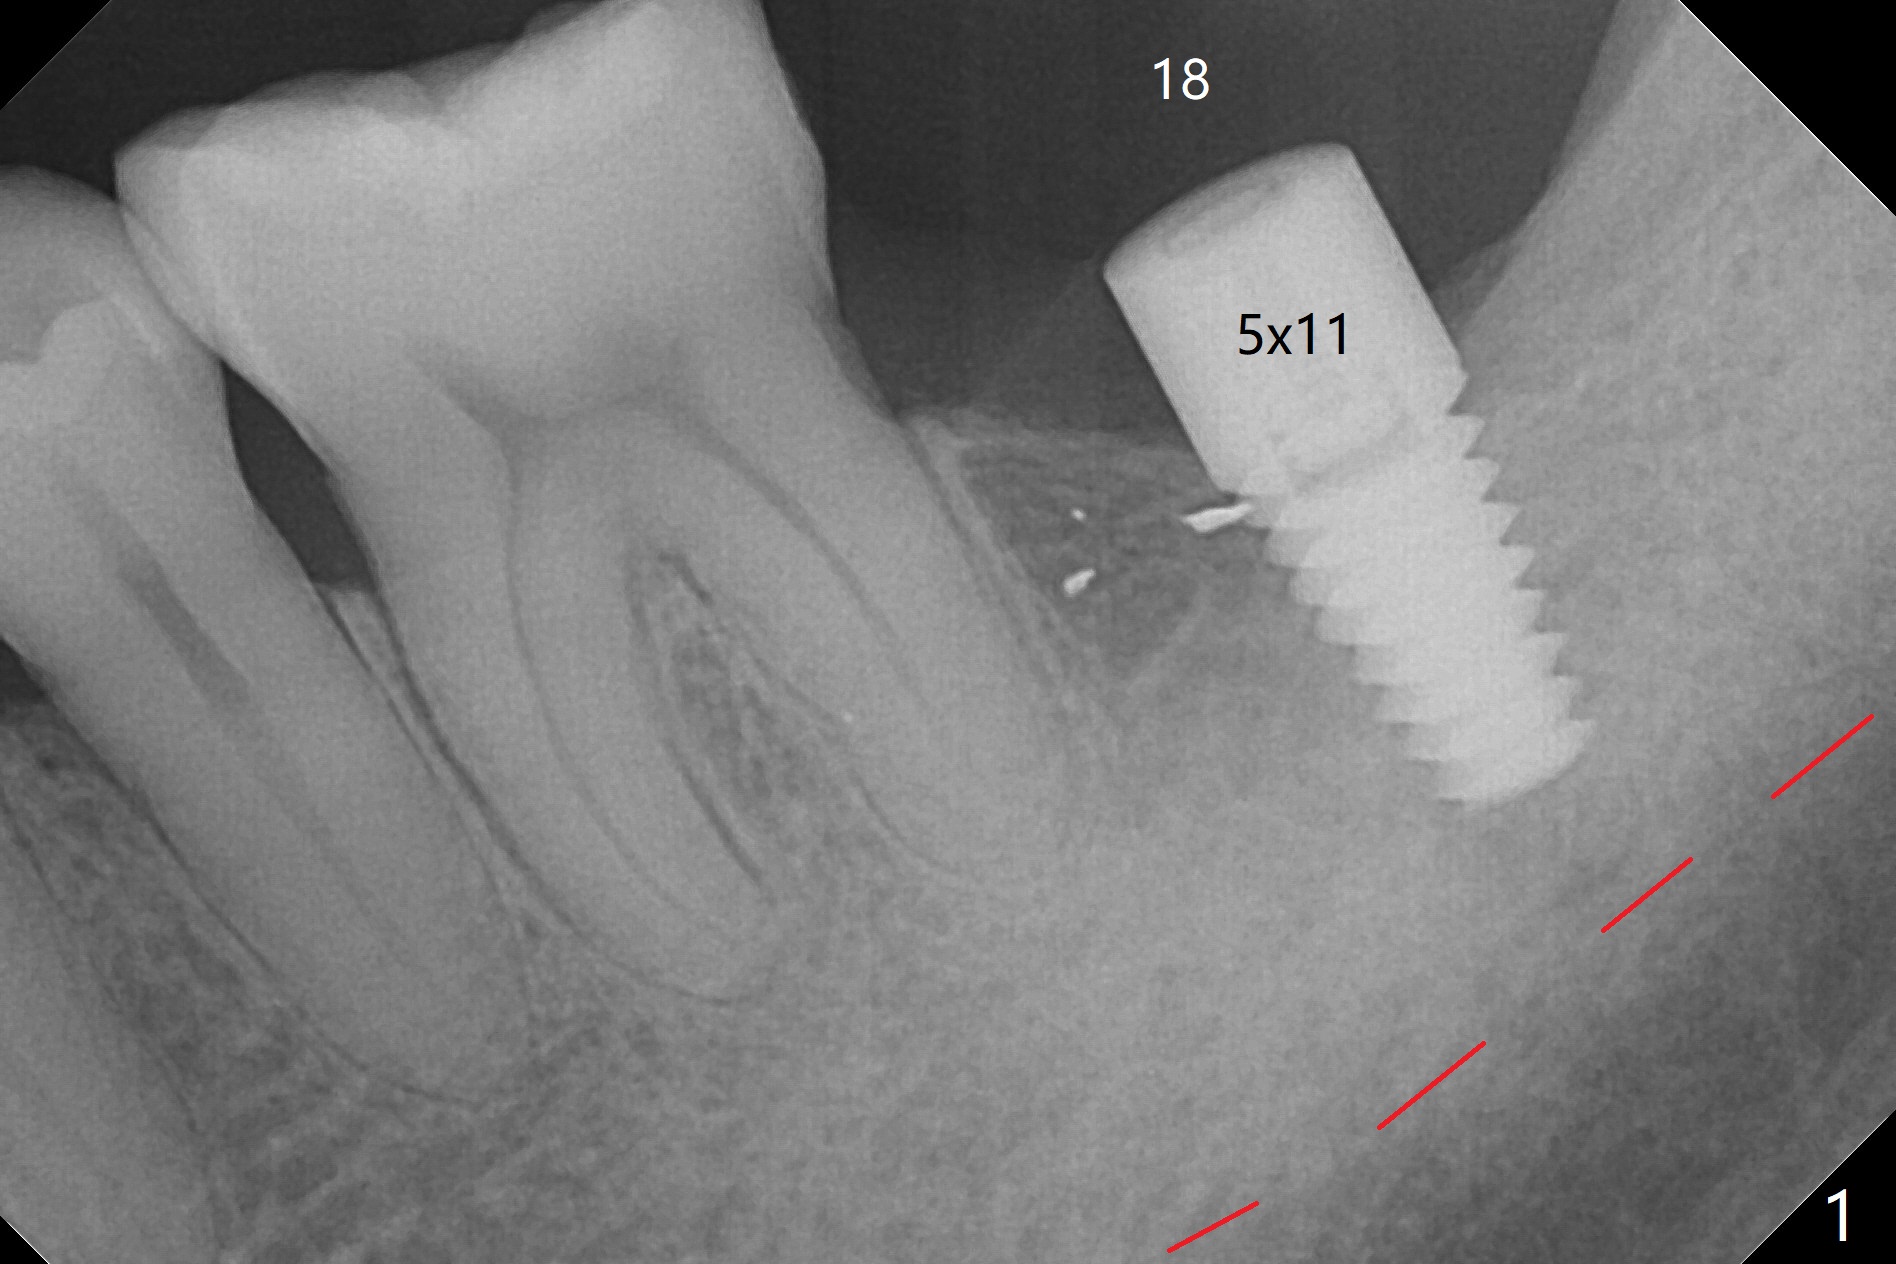

After finishing osteotomy with IS guide and Tatum Tapered tap 5x14 mm for 11 mm (gingival level) free hand, a 5x11 mm Tatum implant is placed at #18 with >15 Ncm (Fig.1). Bone harvested from the site of #18 will be used for #15 sinus lift (Fig.2 * as well as allograft). By the similar fashion, osteotomy at #15 is finished according to IS drill sequence except underdrilling (4.0x7.3 mm drill with 2 O-rings). Following use of DIO Sinus Approach Kit and placement of 2 pieces of PRF membrane and mixture of autogenous and allograft for sinus lift, a 4.5x11 mm IBS dummy implant is placed (Fig.2). With more allograft for sinus lift, a 5x9 mm implant is inserted with >35 Ncm (Fig.3). At #18 the implant 2.5 months postop (Fig.4) seems ok with removal of the cover screw and placement of a healing cuff. The implant at #15 appears osteointegrated with sinus lift 2.5 months postop (Fig.5 *). Half month later, the implant at #18 is tender associated with unipost placement. The healing abutment returns. A pair abutment (5.5x4(4) mm; 25 Ncm) is placed at #15. When the patient returns 7 months postop, BWs are taken to confirm that the abutment at #15 is fully seated, whereas that at #14 is not (Fig.6). A healing abutment is then placed at #14. Osteointegration seems to occur at #18; there is no tenderness when a 4.5x3 mm abutment is placed (Fig.7). Provisional crowns are fabricated at #15 and 18 for progressive loading. When the patient returns 14 months postop, a 5x4(4) mm hex abutment is placed at #14 with apparent gap between the implant and abutment (Fig.8 (PA) open arrow). In fact the gap seems to be absent more coronally as shown by bitewings (Fig.9,10 <). All of the 3 crowns are cemented in situ (Fig.11, 12) although the one at #14 is removed with the abutment for removal of residual cement. When the latter is re-torqued, the abutment remains completely seated (Fig.12). However, the implants at #15 and 18 appear to be placed distally with free-end guides (black lines).